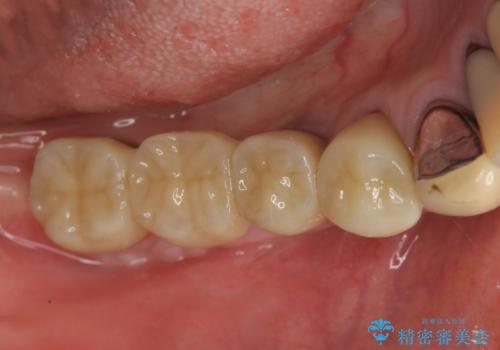

- 110万円(インプラント×2 チタンカスタムアバットメント×2 フルジルコニアクラウン×3 骨増成 歯肉移植)費用は治療当時の料金となります

インプラントを埋入するには十分な骨の量が必要で、吸収して少なくなってしまった場合でも造成できる場合があります。

また、機能したインプラントを長持ちさせるために清掃性を高めるために硬い歯ぐきを移植することは非常に有効です。